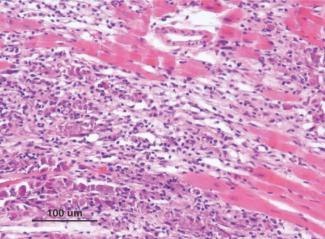

Concepto

Las miocarditis encuadran un grupo de entidades patológicas en las que los microorganismos infecciosos y/o un proceso inflamatorio causan una lesión en el miocardio.

Anatomía patológica

En 1987 se publicaron los llamados criterios de Dallas para el diagnóstico anatomopatológico de la miocarditis. Se describen 3 categorías:

Miocarditis vírica